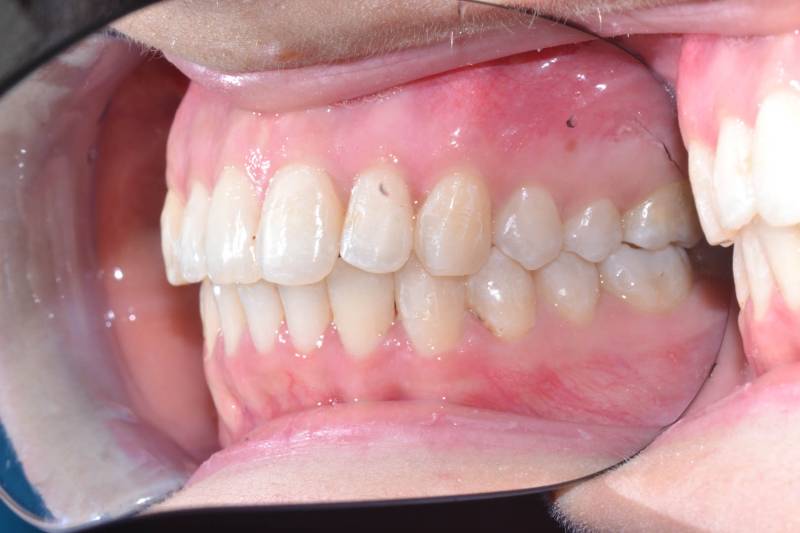

Paziente trattato con ortodonzia tradizionale fissa bimascellare per 20 mesi.